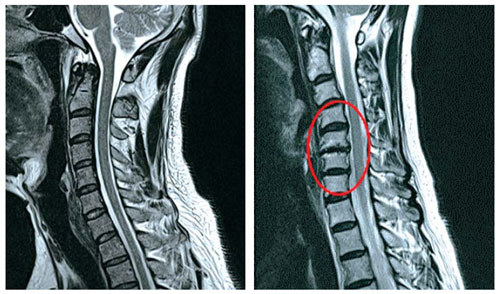

추간판의 수핵이 빠지거나 퇴행성 경추증 및 경추관협착증 등으로 척수가 압박되면 대다수 팔에 힘이 빠지는 것을 느끼게 돼요. 척수가 눌리는 정도이기 때문에 한쪽 팔만 마비될 수 있고요. 하지마는 양팔의 감각이 둔해지고 눈을 감고도 어지럽기 때문에 이러한 목 디스크 증상이 나타나면 무척 위험한 상태가 되기 때문에 빨리 치료가 필요해요.

목디스크 증상 2번째는 다리에 힘이 빠지거나 걷기 곤란한 보행장애가 보여집니다니다. 목디스크 증상은 거의 퇴행성 질환으로 40대부터 조금씩 증상이 생기는 경우가 많이 들어있습니다 이는 그릇된 생활습관이나 오랜시간 앉아있을 때 디스크를 비집고 나온 수핵이 척수를 압박해 신경을 누르게 되어 통증을 느끼게 된다 하였습니다. 증상의 순서의 경우 손에 힘이 빠지고 저리다가, 다리까지 힘이 빠져 걷기 쉽지 않은 보행장애가 생겨나게 된다고 합니다.